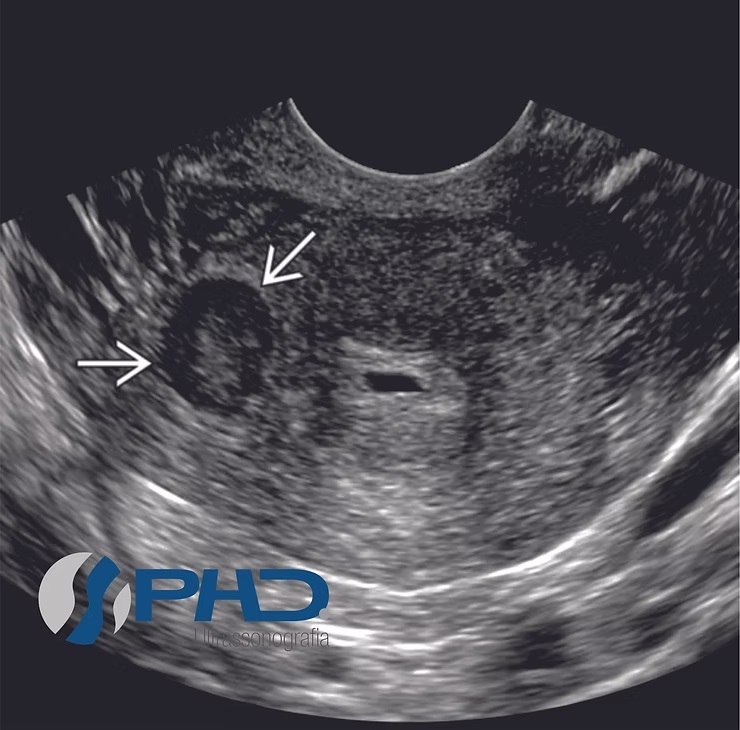

Qual o diagnostico

A

Mioma

Q

Qual o diagnótico

18

pólipo

qual o diagnóstico

20